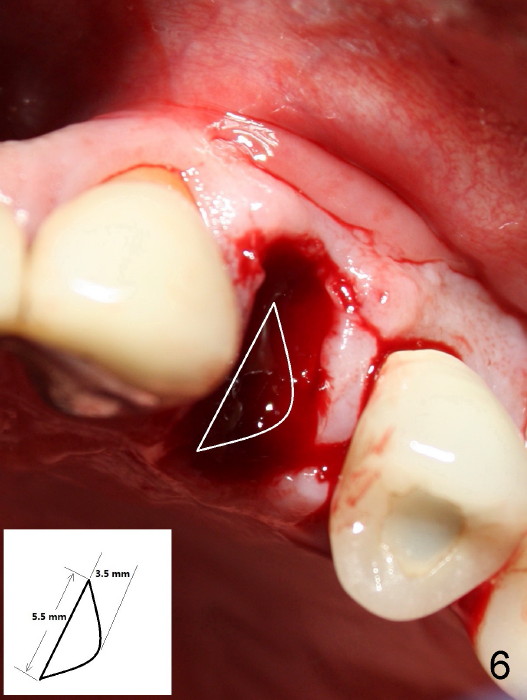

The socket of an upper first premolar is oval (Fig.5), whereas majority of implants are rounded. It is always a mismatch. An implant that matches the shape of the socket most closely is "D" Plateau Implant (Fig.5 insert, Fig.6). The D implant that is appropriate for your case is called D2. It is 20 mm long (Fig.4). On cross section is 5.5 mm wide and 3.5 mm tall at crest (widest portion, Fig.6 insert). The D implant is tapped in. Immediate provisional can be installed. Are you interested in the D implant? Crown forms are needed for the provisional.